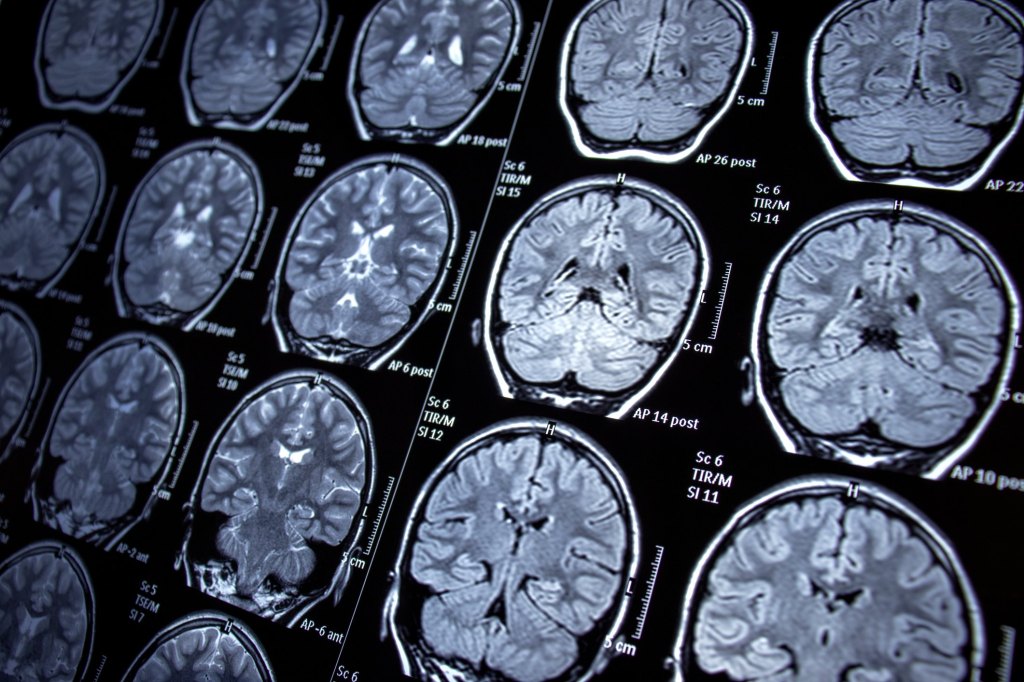

neuro-imaging and explainable ai

We are researching on using Graph Theory and AI to quantify the regional brain atrophy in the fMRI images.